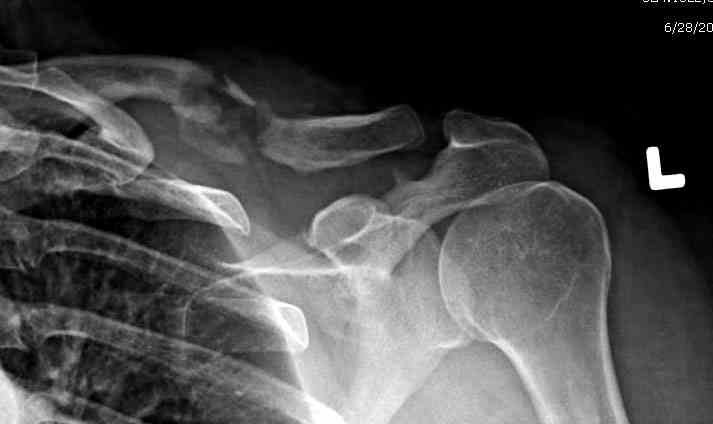

iГГШ> выполнения новокаиновой блокады дежурной бригадой выполнена закрытая

ГГШ> репозиция, наложены кольца Дельбе. Результаты репозиции показаны на

ГГШ> Результат стационарного лечения приведен на рентгенограмме (Xray_3).

Это картинка то есть через неделю после травмы, при выписке? Более чем приемлемо.

1) после репозиции стало хуже

2) стояние фрагментов при выписке идентично таковому при пступлении - с выраженным смещением

Ув. Г.В.! На мой взгляд, никакого ухудшения стояния отломков на втором снимке нет!!! Просто проекция среднего снимка несколько под другим углом, и увеличение межотломкового расстояния не что иное , как проекционное искажение. По - поводу колец... Конечно они иммобилизуют плечо лучше , чем Cuff and Collar, хотя не намного, но что если разовьётся парез брахиального сплетения???

Уважаемая Г.В. Полностью согласен с Вашим постом.Закрытая репозиция и кольца Дельбе отлично зарекомендовали себя за 35 лет практики. В обсуждаемом случае представленные Р-граммы сами говорят за себя, 1 снимок (до лечения) и 3 снимок (после лечения) абсолютно идентичны, 2 снимок сделан в несколько иной позиции.Как говорится "комментарии излишни". Согласитесь, что результат лечения мог бы быть и лучшим.